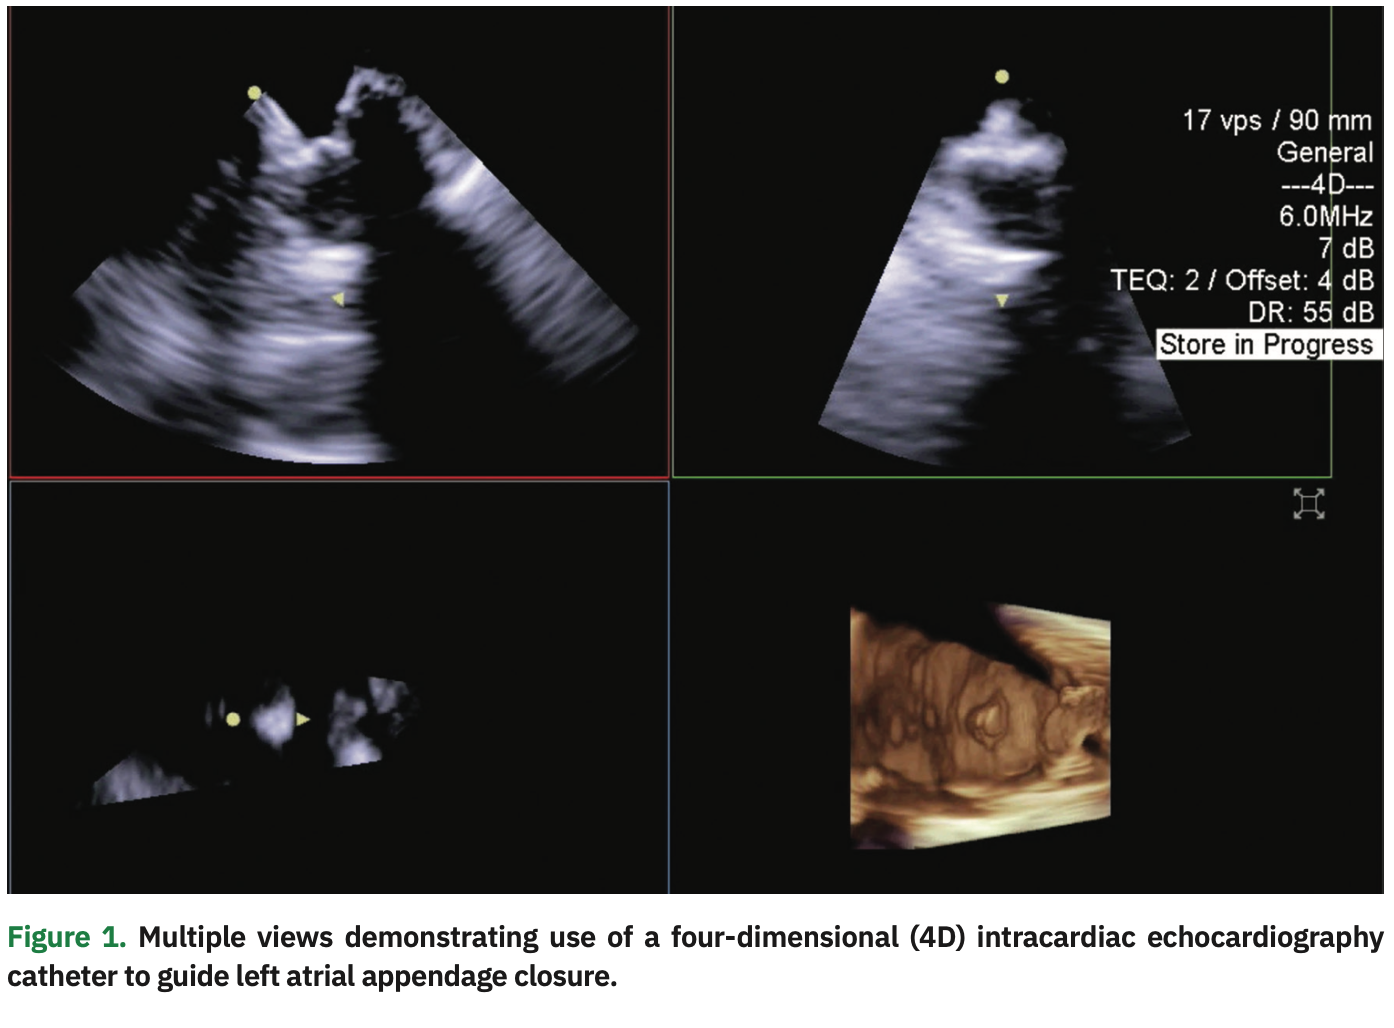

In early 2020, we began adopting preprocedural CT angiography imaging prior to our scheduled LAA closure case days to facilitate same-day discharge, eliminate the use of general anesthesia, and incorporate intracardiac echocardiography (ICE). We are increasingly using ICE during EP procedures to view cardiac structures, guide transseptal catheterization, evaluate the position of ablation catheters, assess for occlusion of the pulmonary vein during cryoballoon ablation, and exclude complications such as pericardial tamponade and thrombus formation.5 TEE can also be used to guide cardiac interventions and is commonly used during structural heart procedures such as percutaneous valve interventions and LAA closures. One major disadvantage of using a TEE probe to guide EP procedures is the need for and complications associated with general anesthesia in the elderly population. Over the last 3 years, we have been using a 2D ICE catheter placed in the left atrium to guide LAA closures.6 In addition, we very recently began using a four-dimensional (4D) ICE catheter to guide LAA closure, and present a brief case below (Figure 1). We are also excited about the possibility of newer ablation modalities such as pulsed field ablation.

Case Presentation: LAA Closure Using 4D ICE

A 78-year-old female with a significant past medical history of permanent nonvalvular AF, hypertension, diabetes, and vascular disease was recently referred for LAA closure. She suffered from esophageal strictures and a large hiatal hernia. Due to her comorbidities, the patient was not ideal for long-term anticoagulation. Therefore, it was determined to proceed with conscious sedation and ICE for Watchman device (Boston Scientific) implant. CT angiography prior to the scheduled procedure was obtained for sizing as well as for guiding transseptal puncture. Precise measurement of the landing zone was performed using the ACUSON AcuNav 4D Volume ICE Catheter and ACUSON SC2000 PRIME ultrasound system (Siemens Healthineers), and the Watchman device was implanted with no complications. The groin was closed using a figure-of-8 stitch and the patient was placed on 3-hour bedrest. Once the suture was removed from the groin and the patient demonstrated appropriate hemostasis of the groin, the patient was discharged from the hospital on the same day of the procedure.